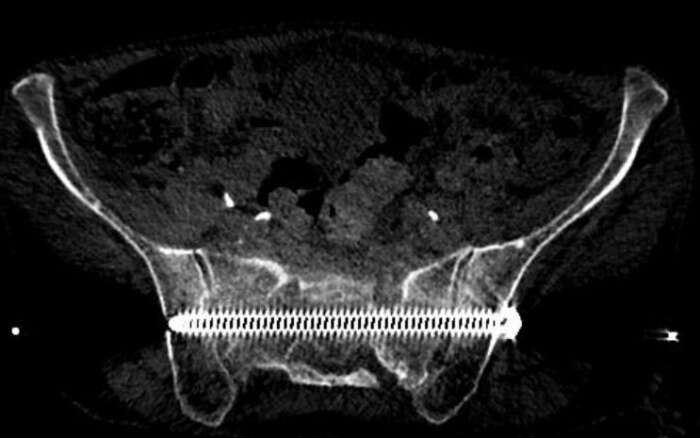

In diesem Beispiel war die Patientin vier Wochen nach einem Sturz nur noch mit Krücken und mit Schmerzen mobil. Die Computer Tomographie (CT) zeigte einen nicht verschobenen Bruch des Kreuzbeins und eine leicht verschobene Fraktur des Schambeins. Während der Operation implantierten wir CT-gesteuert zwei 7,3-mm-Schrauben. Die Schrauben gingen durch beide Ilio-Sakralgelenke und erste und zweite sakrale Wirbelkörper. Die Patientin konnte am nächsten Tag nach Hause entlassen werden und war schmerzfrei mobil.

Implantation einer 7.3 mm Schraube quer durch das Kreuzbein. Die Rückenmarks-Nerven können Millimetergenau geschont werden

Röntgen Becken nach Implantation zweier 7.3 mm Schrauben quer durch das Becken und Kreuzbein